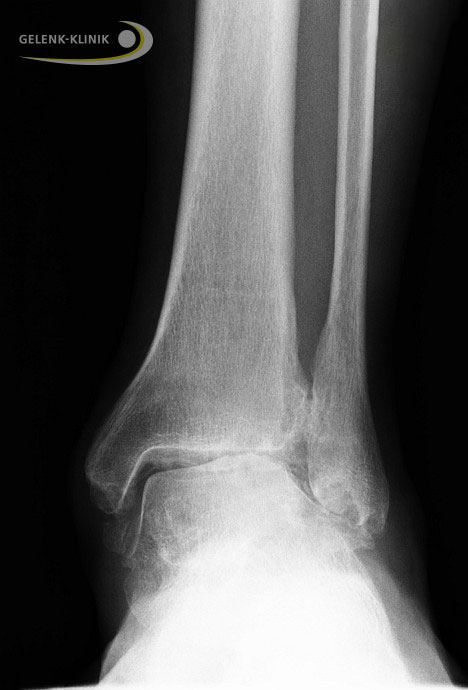

Röntgen

Eine Röntgenaufnahme kann Fehlstellungen der am Gelenk beteiligten Knochen darstellen. Grundsätzlich sollten Belastungsaufnahmen der Sprunggelenke im Stehen und in zwei Ebenen durchgeführt werden. Der Spezialist kann den Gelenkspalt beurteilen und damit den Zustand des Gelenkknorpels bewerten. Die Aufnahmen liefern wichtige Hinweise für das Vorliegen einer Wadenbeinverkürzung und knöcherner Fehlrotationen. Auch eine Ausrenkung (Luxation) des Gelenks wird durch die Röntgenaufnahme sichtbar.